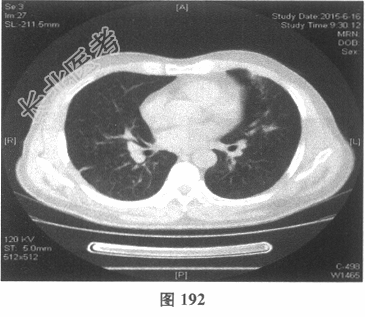

- 多项选择题4.[提示]患者应用多种抗生素治疗(第三代头孢菌素、青霉素加酶抑制剂)包括抗曲霉菌治疗无效,加用甲泼尼龙40mg静脉滴注病情好转。肺部CT检查显示病变明显改善。尿常规检查正常, 肾功能检测正常。复查肺部CT(图188~图195):示病变较前好转。Wegener肉芽肿的主要临床表现是( )

C、肺部CT常见肺内多发团块状影,常见空洞